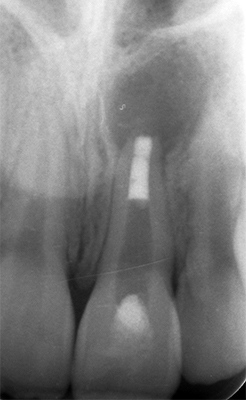

Fig. 05 et 06 : détermination de la longueur de travail et radiographie rétro alvéolaire lime en place.

La longueur de travail estimée préalablement sur la radiographie pré-opératoire est confirmée à l’aide d’une radiographie lime en place.

Après retrait du Ca(OH), le fouloir de Machtou utilisé pour l’obturation apicale est calibré. Ce dernier doit attendre la longueur de travail moins 2 mm sans contrainte(5). Une radiographie rétro alvéolaire permet de s’assurer du bon calibrage du fouloir.

Fig. 09 : radiographie de calibrage du fouloir.